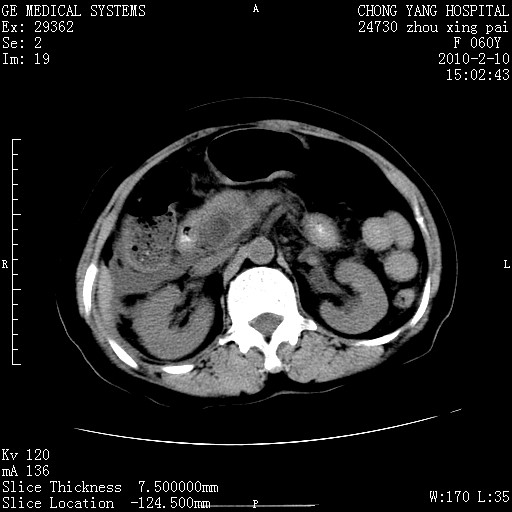

标题: CT24682:F60Y 腹痛 其它不详 [打印本页]

标题: CT24682:F60Y 腹痛 其它不详

胆总管末端梗阻!结石?胰腺影增粗,以胰腺头部为著,胰周看见渗出影,双侧胸腔积液,(胸膜反应)考虑胰腺炎。

1)胆总管末端梗阻,不排除结石所致可能。2)胰腺炎。3)慢性胆囊炎可能。4)左侧输尿管上段扩张。5)少量腹水。6)双侧少量胸腔积液,伴两下肺部分肺萎陷。

1)胆囊炎。2)胆源性胰腺炎。3)右肾周筋膜增厚,肾旁前间隙积液。4)左侧输尿管上段扩张。5)少量腹水。6)双侧少量胸腔积液,伴两下肺部分肺膨胀不全。

1)胆总管末端梗阻。2)胰腺炎。3)慢性胆囊炎可能。4)左侧输尿管上段扩张。5)少量腹水。6)双侧少量胸腔积液,伴两下肺部分肺萎陷。